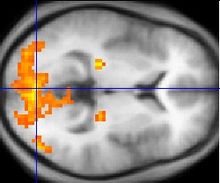

Asperger syndrome appears to result from developmental factors that affect many or all functional brain systems, as opposed to localized effects. Although the specific underpinnings of AS or factors that distinguish it from other ASDs are unknown, and no clear pathology common to individuals with AS has emerged, it is still possible that AS's mechanism is separate from other ASDs. Neuroanatomical studies and the associations with teratogens strongly suggest that the mechanism includes alteration of brain development soon after conception. Abnormal migration of embryonic cells during fetal development may affect the final structure and connectivity of the brain, resulting in alterations in the neural circuits that control thought and behaviour. Several theories of mechanism are available; none are likely to provide a complete explanation.

The underconnectivity theory hypothesizes underfunctioning high-level neural connections and synchronization, along with an excess of low-level processes. It maps well to general-processing theories such as weak central coherence theory, which hypothesizes that a limited ability to see the big picture underlies the central disturbance in ASD. A related theory—enhanced perceptual functioning—focuses more on the superiority of locally oriented and perceptual operations in autistic individuals.

The mirror neuron system (MNS) theory hypothesizes that alterations to the development of the MNS interfere with imitation and lead to Asperger's core feature of social impairment. For example, one study found that activation is delayed in the core circuit for imitation in individuals with AS. This theory maps well to social cognition theories like the theory of mind, which hypothesizes that autistic behaviour arises from impairments in ascribing mental states to oneself and others, or hyper-systemizing, which hypothesizes that autistic individuals can systematize internal operation to handle internal events but are less effective at empathizing by handling events generated by other agents.